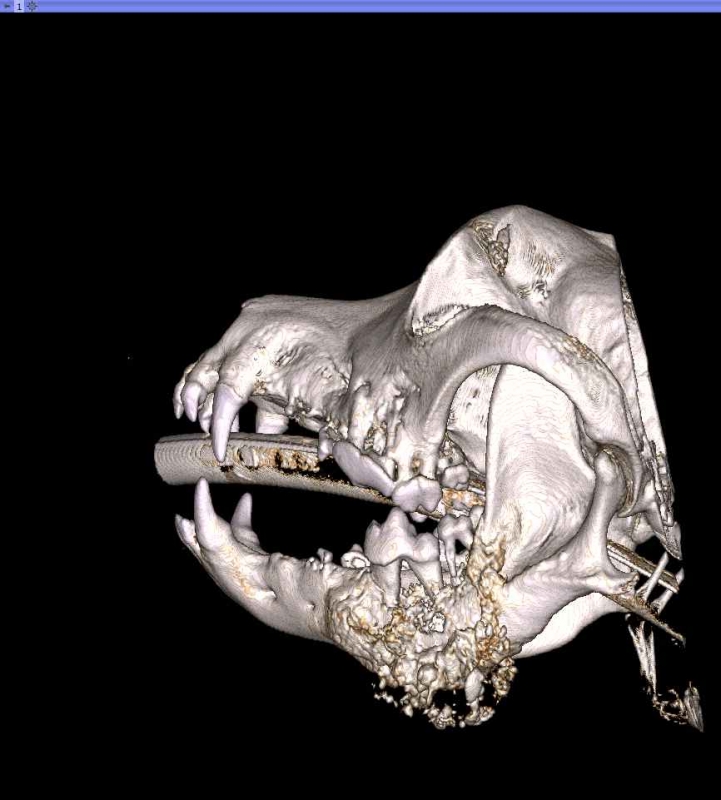

The Center now provides advanced imaging via cone beam CT. Cone beam CT is excellent for visualization of bony structures of the skull, nasal cavity, teeth, and ears. Cone beam CT is especially helpful for diagnosing dental disease and evaluation of jaw fractures. It can also be useful for evaluating the sinuses and tympanic bulla. Cone beam CT can be used in conjunction with nasal biopsy and culture to evaluate nasal discharge whether chronic or acute.

Pets can be involved in trauma that can cause fractures to their head, teeth, and jaw bones. Correctly repairing these fractures is extremely important for your pet to have normal function of their mouth. If a jaw fracture is allowed to heal in an abnormal position, your pet may have great difficulty chewing and can be in significant pain. Many fractures can be successfully treated with minimally invasive oral procedures, but more complicated cases may require bone plating techniques. The Center offers cone beam CT imaging which provides extremely detailed images of the bones of the head and skull. Advanced imaging with CBCT facilitates selection of the best surgical technique to get your pet back to eating and comfort as soon as possible.